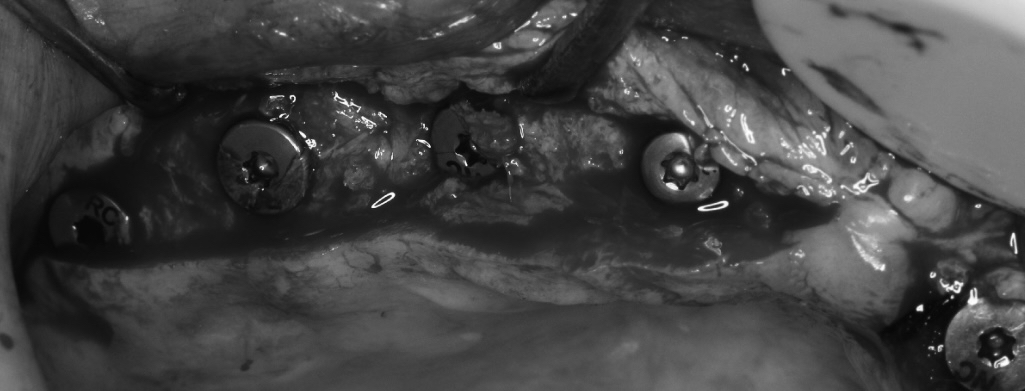

该患者就是因牙周病导致牙齿松动脱落,我们通过在半口牙槽骨上植入8颗种植体,然后在种植体上安装连桥牙冠,从而恢复半口牙齿的咀嚼功能和美观。相对于传统的种植修复方式缺一颗种一颗。4-8颗种植体的种植手术创伤相对较小,大大的减少了患者的疼痛感。